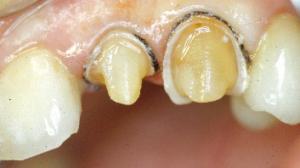

Une préparation coronaire périphérique a déjà été réalisée sur la 22.

Préparation de la 23. Réalisation d'un sillon qui suit le périmètre de la face vestibulaire avec une fraise boule de 1mm.

La fraise boule est enfoncée à moitié. Ce sillon aura donc une profondeur d’environ 0,5 mm. Au collet, le sillon est pour le moment nettement éloigné de la gencive.

La préparation de la face vestibulaire est terminée. La limite est pour le moment supra gingivale.

Les limites de préparation sont actuellement juxta-gingivales.